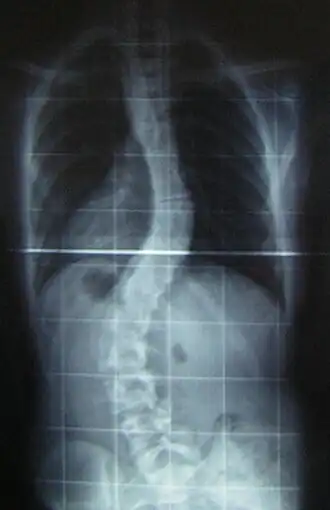

Radiografía de una joven de 16 años y 8 meses con escoliosis vista de frente, de pie y con ropa (los pendientes y los aros del sostén son claramente visibles) | ||

Es habitual que cuando se sospecha de escoliosis, se tomen radiografías del tórax en planos anteroposterior/coronal, y lateral/sagital, para evaluar las curvas de la escoliosis, además de las curvas normales de cifosis y lordosis, ya que estas también pueden estar afectadas en personas con escoliosis. Los rayos X de la columna en un paciente de pie, son el método estándar para evaluar la severidad y progresión de la escoliosis, y si es de naturaleza congénita o idiopática. En individuos en crecimiento, las radiografías seriales se obtienen en intervalos de 3-12 meses para seguir la progresión de la curvatura, y en algunos casos, se necesita además de resonancia magnética para examinar la médula espinal.